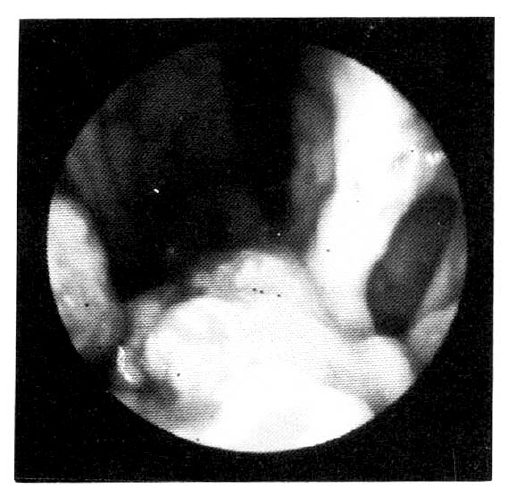

Endoscopy was performed with olympus GIF PIO. A large nodular mass was noted on the anterior wall and lesser curvature aspect of the body 2 cm above the stoma. The mass had superficial ulcerations and was easily bled to the touch. Endoscopic examination of the jejunal side was normal (Fig. 2).

Fig. 2.

A large nodular mass was noted on the anterior wall an lesser curvature aspect of the body 2 cm above the stoma. The mass had superficial ulcerations and bled easily to the touch. Endoscopic examination of the jejunal side was normal.